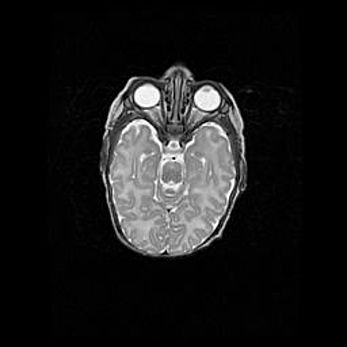

Церебральная ишемия II.

Возраст: 5 дней

Вес: 3400 г

Пол: женский

Окружность головы: 35 см

Срок гестации: 39 недель

Церебральная ишемия – это заболевание, характеризующееся недостаточностью (гипоксией) либо полным прекращением (аноксией) снабжения мозга кислородом по причине закупорки одного или нескольких сосудов. Это приводит к  что метаболическим расстройствам различной степени тяжести в тканях головного мозга, развитию коагуляционных некрозов и гибели нейронов.